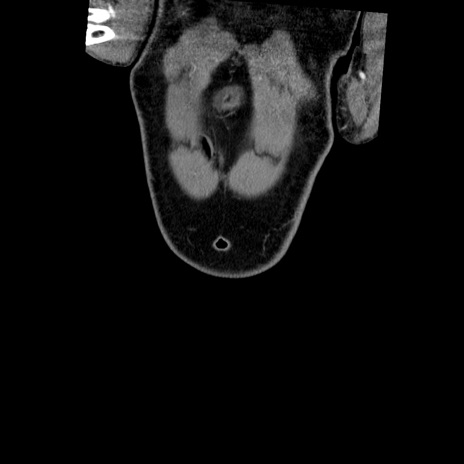

横断像

【症例】50歳代男性

【主訴】腹痛

【現病歴】AVMからの被殻出血のため回復期リハ病棟入院中。 本日午後3時頃急に下腹部痛が出現した。

【既往歴】AVM、被殻出血、虫垂炎、高血圧

【身体所見】意識晴明、左半身不全麻痺、会話の理解は良好、36.5°C、腹部:膨隆、全体に板状硬、下腹部正中に圧痛点あり、反跳痛-、筋性防御不明、右下腹部にope scar

【データ】WBC 9400、CRP 0.06